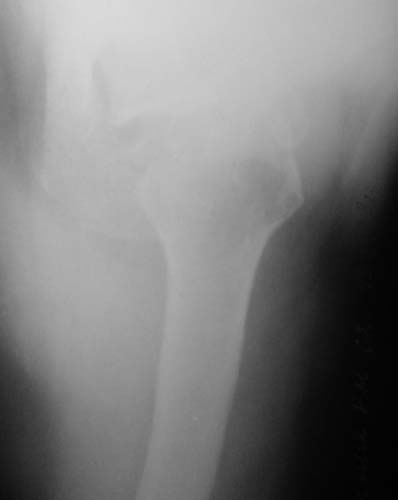

Уважаемые коллеги!Женщина, 60 лет. 3 недели назад упала с упором на отведенную левую руку. Почувствовала боль в левом плечевом суставе. За помощью не обращалась. 2 недели "мази и припарки". Затем - рентгенограмма (r1 и r2), жалобы на боли,ограничение движений...

Активное отведение 80 гр., при пальпации - головка плечевой кости безболезненно вправляется и тут же самостоятельно вывихивается. Наложена косыночная иммобилизация, рентгенография (r3) и МРТ.В нашем диагностическом центре МРТ исследование плечевого сустава выполнено впервые, опыта у нас маловато :(.Вопросы: уточнение диагноза? какие исследования провести? тактика лечения?

"Прицельная" съемка малопонятного очага.

1. На рентгене - нижний подвывих плеча и очаг остеолиза суставного бугорка с четкими контурами (вдавленный перелом на фоне остеопороза ? доброкачественная опухоль? аваскулярный некроз ? (хотя ни разу не слышал об аваскулярном некрозе плеча..)